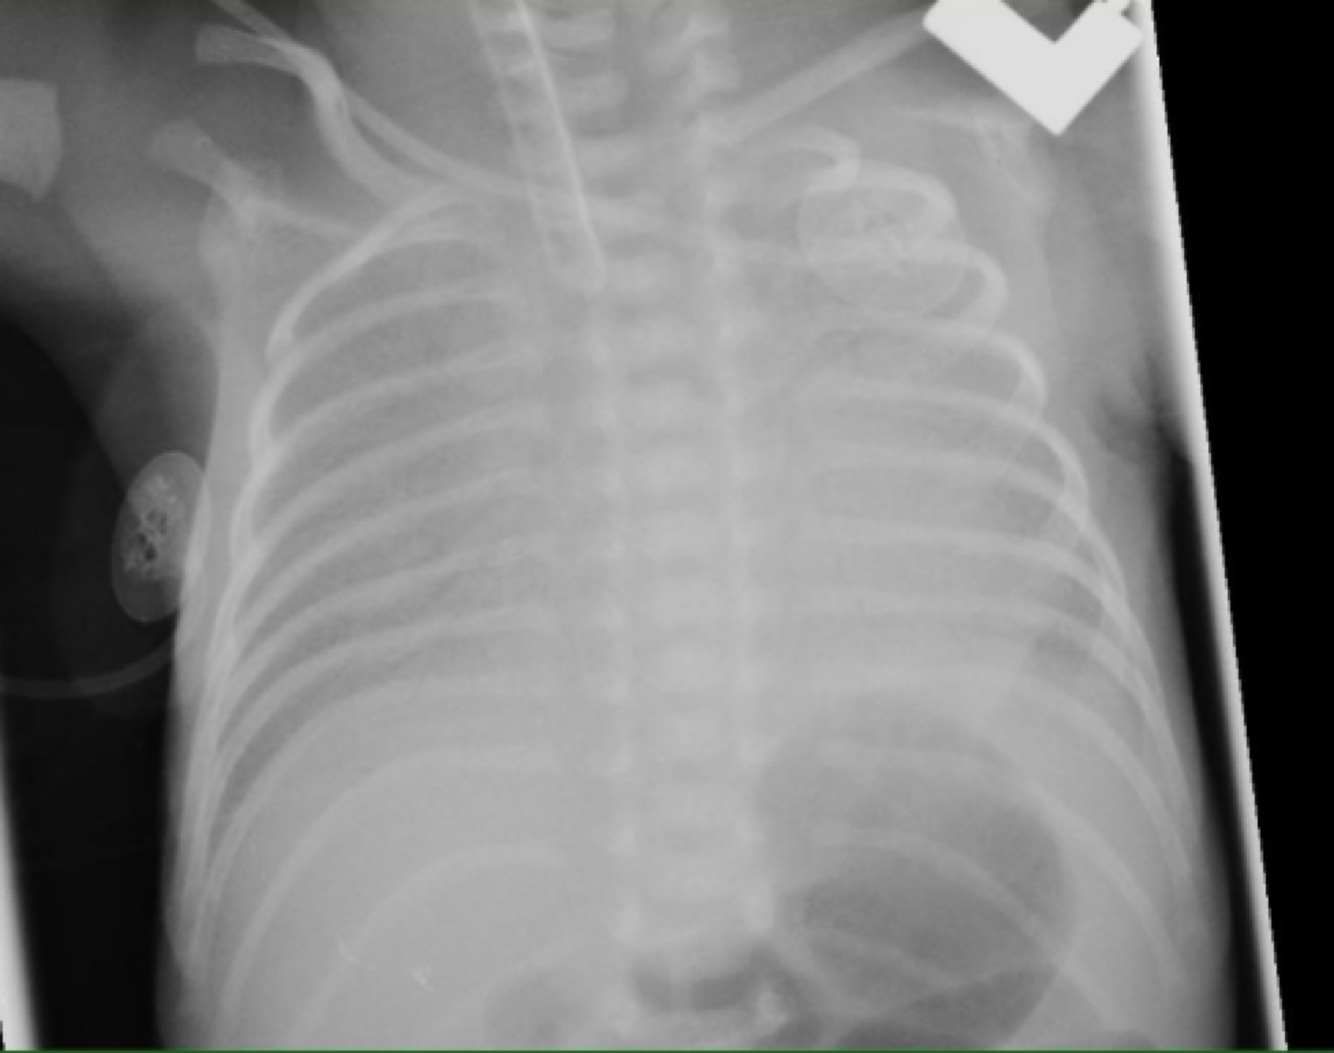

Tracheoesophageal fistula : distended gastric bubble and the nasogastric tube that has not reached the stomach but has rather coiled in the mediastinum

congenital diaphragmatic hernia